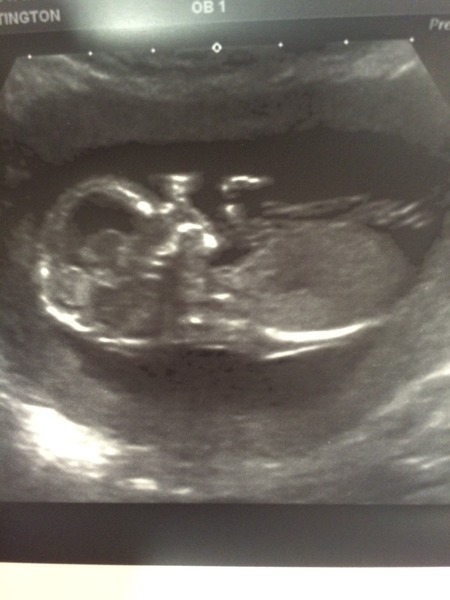

sparkly Lovely picture!